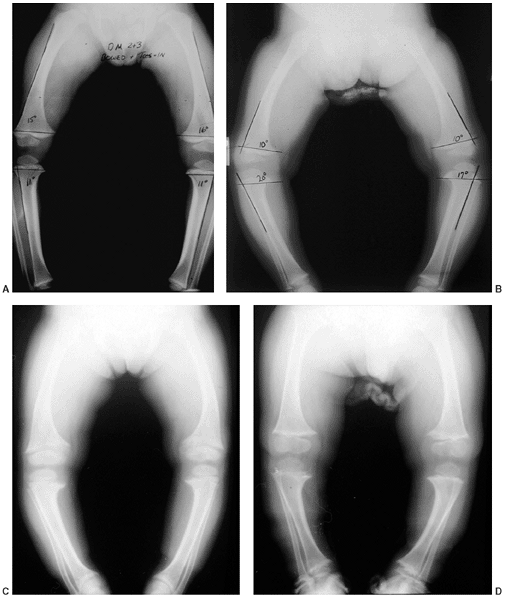

radiographs can document the degree and location of the varus

percentile), or if a metabolic bone disease is suspected (Fig. 28.8).

is noted by observing the shaft-to-shaft angle of the femur and tibia (51,52). More importantly, the distribution of bowing deformity is noted (53). When physiologic, the bowing occurs throughout the distal femur, proximal tibia, and distal tibia (54). In contrast, early Blount disease has more focal deformity limited to the proximal tibia.

B–D). The clinical and radiographic features associated with metabolic

may be present (54,55,56).

![]() |

|

Figure 28.8 Standing anteroposterior films of both lower extremities help distinguish physiologic bowing from pathologic causes. A:

Tibial metaphyseal-diaphyseal (MD) angles are typically 11 degrees or less. A similar angle constructed in the distal femur is the same or greater, indicating that the femur and tibia contribute similarly to the bowing. The ratio of femoral to tibial MD angle is greater than 1. B: Early Blount disease may be difficult to distinguish from severe physiologic bowing. The MD angle in Blount disease is usually greater than 16 degrees and the ratio of femur to tibia is less than 1. Fragmentation of the medial tibial metaphysis may not be evident. C: This patient with X-linked hypophosphatemic rickets (XLH) has multiple widened physes. Osteopenia is evident in the adjacent metaphysis, which is also flared. Bowing tends to be more diffuse throughout the bone rather than focal in the proximal tibia. D: Skeletal dysplasia, such as chondrometaphyseal dysplasia, may cause genu varus. These children are usually of short stature. Skeletal abnormalities are multifocal as in this example of Schmid metaphyseal chondrodysplasia. The proximal and distal metaphyses of the femur and tibia are all abnormal. The epiphyses, physes, and bone density are normal. |